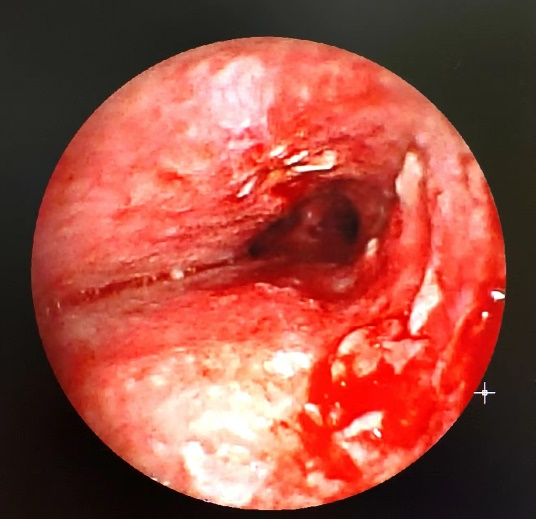

術前

次日,通過結核科、ICU、氣管鏡、麻醉科、影像科多學科MDT討論,發(fā)現(xiàn)氣管明顯狹窄,且有氣管內(nèi)新生物阻塞的情況。

第一種方式:急診氣管鏡介入手術,采取腫塊熱消融術或者放置支架,把氣管撐起來,改善患者通氣。但是,這個手術存在多個挑戰(zhàn)和風險,包括患者體位難以平臥、通氣困難、腫塊臨近主動脈、缺乏增強CT信息、以及對新生物性質和出血風險的不確定性??墒牵绻皇中g,患者的通氣問題無法得到解決,更嚴重的是氣管新生物可能會破裂導致出血。

第二種方式:氣管插管,先保證通氣,再找病因。但是插管容易把氣管內(nèi)腫塊插破導致大出血。插管時如果沒有越過這個腫塊,通氣效果還是不好。如果不找到病因,解決梗阻的根本問題,患者的治療效果同樣不好。

此時,氣管鏡和麻醉團隊,考慮患者年輕,身體有一定抵抗基礎,患者意志力強,面對積極向上的生命,與其被動等待,不如主動出擊。選擇采取“氣管鏡探查+腫塊介入熱消融術”為患者急診手術。